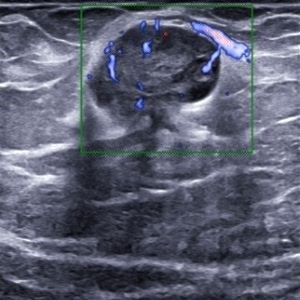

Eine erste Untersuchung ergab einen suspekten Tastbefund an der linken Brust. Die folgende Sonografie einen Tumor; Verdacht auf Malignon (Abb. 1, 2). Die durchgeführte Duplex- (Abb. 3) und 3D-Songrafie (Abb. 4) sowie die Elastografie (Abb. 5) erhärtete die Verdachtsdiagnose.

Abb. 1

Abb. 2